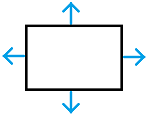

Два базовых понятия, без которых не обойтись: для пересекающихся выпуклых многоугольников mtv-вектор (minimum translation vector) — это наименьшее смещение одного из многоугольников, после которого пересечение прекращается.

Ещё нам потребуются нормали многоугольника — в 2D они перпендикулярным граням и указывают “наружу”: